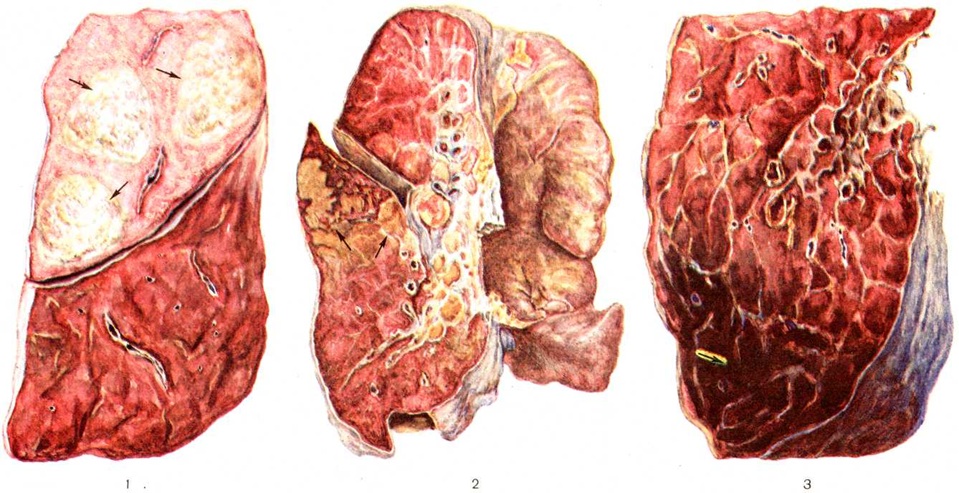

При пневмококковой Пневмония, в частности при её наиболее тяжёлом варианте — крупозной Пневмония, процесс начинается с развития небольшого очага серозного воспаления, располагающегося обычно в задних или в заднебоковых отделах лёгких, где содержатся пневмококки (рисунок 2, а). Патологический процесс распространяется прежде всего контактным путём и очень быстро захватывает значительную часть лёгкого — целую долю и даже несколько долей. Макроскопически лёгкое увеличено в объёме, его ткань резко отёчна и полнокровна. Эти изменения носят название стадии прилива.

В дальнейшем в экссудате нарастает количество нейтрофильных лейкоцитов, нередко одновременно с фибрином серозно-гнойный экссудат постепенно заполняет просветы альвеол (рисунок 2,6); последние достигают при этом размеров, которые они имеют на вдохе; пневмококки в это время фагоцитируются лейкоцитами и исчезают. При прогрессировании болезни более выраженные нарушения определяются на границе с неизменённой тканью органа. На разрезе лёгкое серого цвета с мелкозернистой или гладкой поверхностью, по консистенции напоминает печень (серая гепатизация лёгкого). У больных с повышенной проницаемостью сосудов к экссудату присоединяется большое количество эритроцитов, в результате чего лёгкое приобретает серо-красный или темно-красный цвет (красная гепатизация лёгкого).

В период выздоровления происходит рассасывание выпота; макроскопически в этот период лёгкие характеризуются пониженной воздушностью и эластичностью.

При очаговой пневмококковой Пневмония отмечаются сходные изменения, но с меньшей степенью выраженности.

Стафилококковая Пневмония имеет ряд особенностей. На ранних стадиях заболевания вокруг скоплений стафилококков появляется серозный или чаще серозно-геморрагический экссудат с небольшой примесью нейтрофильных лейкоцитов. В дальнейшем очаги воспаления приобретают характерное зональное строение.

В центре их содержится много стафилококков, возникают некротические изменения (рисунок 3, а), вокруг участков некроза накапливаются лейкоциты, которые фагоцитируют стафилококки. В периферических участках пневмонического очага альвеолы содержат фибринозный или серозный экссудат, в котором нет бактерий. При тяжёлом течении болезни (стафилококковой деструкции лёгких) в местах скоплений стафилококков на значительном протяжении происходит разрушение лёгочной ткани. Макроскопически в лёгких выявляются множественные мелкие, нередко сливающиеся очаги абсцедирующей Пневмония Они красного или темно-красного 4 цвета с желтовато-серыми участками расплавления в центральной части. Позднее здесь формируются абсцессы,. принимающие иногда хронический течение. При распространении инфекционные процесса на плевру и её деструкции возникает сообщение между полостью абсцесса, бронхами и плевральной полостью, развивается пиопневмоторакс (смотри полный свод знаний). Иногда в результате деструкции стенки бронха и проникновения воздуха в интерстиций возникает интерстициальная эмфизема.

Стрептококковая Пневмония имеет много общих черт со стафилококковой. Однако в тяжёлых случаях она характеризуется большей степенью некроза клеток экссудата и лёгочной ткани, а также более выраженной лимфогенной генерализацией процесса.

Для Пневмония при острых вирусных респираторных инфекциях (гриппе, парагриппе, респираторно-синцитиальной и аденовирусной) наиболее характерно поражение эпителия слизистой оболочки дыхательных путей и альвеолоцитов. В результате внутриклеточного размножения вирусов происходит повреждение этих клеток с развитием дистрофических и некротических изменений. При благоприятном течении заболевания через несколько дней в них возникают реактивные изменения в виде уплотнения цитоплазмы вокруг участка повреждения — фуксинофильные включения) (рисунок 3, б). Наряду с этим наблюдаются умеренно выраженные воспалительные изменения слизистой оболочки дыхательных путей с преобладанием нарушений кровообращения в виде полнокровия сосудов, выпотевания серозной жидкости в просвет альвеол и небольших кровоизлияний. Отмечаются также небольшие скопления нейтрофильных лейкоцитов и альвеолярных макрофагов. В результате нарушения образования сурфактанта (смотри полный свод знаний) возникают небольшие ателектазы (смотри полный свод знаний), большей частью неполные,— дистелектазы (рисунок 3, в), что особенно выражено у детей раннего возраста, а также компенсаторное очаговое расширение альвеол в других участках лёгких. Макроскопические изменения при этом незначительны и заключаются в основном в катаральном воспалении дыхательных путей и образовании в лёгких небольших участков уплотнения темно-красного или синюшного цвета. Наиболее характерной чертой вирусной Пневмония является гигантоклеточное превращение поражённых эпителиоцитов.

При гриппе поражённые клетки несколько увеличиваются в объёме, в случае же отторжения превращаются в крупные одноядерные клетки, значительно превышающие по размерам обычные альвеолярные макрофаги (рисунок 3, г). Для парагриппа типичны подушкообразные разрастания, сосочковидные выросты слизистой оболочки. При респираторно-синцитиальной инфекции они ещё более выражены. При аденовирусной Пневмония происходит образование крупных одноядерных клеток (гигантоклеточный метаморфоз альвеолоцитов), а также выраженное накопление экссудата (рисунок 3, д). При выздоровлении происходит регенерация эпителия дыхательных путей. Вначале выявляются недифференцированные уплощённые эпителиальные клетки, располагающиеся обычно в несколько рядов (рисунок 3, е), которые в дальнейшем дифференцируются .

Изменения, сходные с морфологический изменениями при вирусной Пневмония, наблюдаются при микоплазменной Пневмония — респираторном микоплазмозе (смотри полный свод знаний Микоплазменные инфекции). Для неё также типично внутриклеточное размножение возбудителя (рисунок 4), хотя возможно и внеклеточное. Поражения носят характер десквамативной Пневмония при весьма умеренных макроскопических изменениях (цветной рисунок 3—5; 6—10).